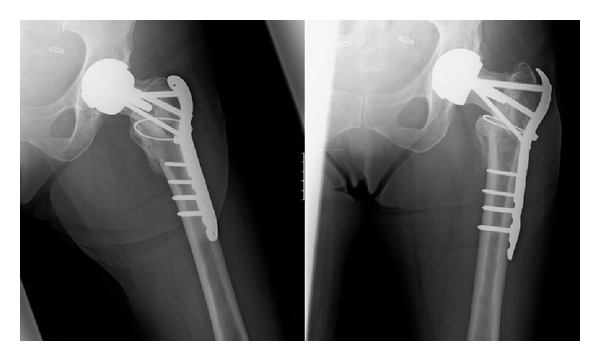

Mrs. X was reviewed six weeks post-operatively and it was noted that her fracture had collapsed slightly and the hip had slipped into a more varus position (see Figure 5). At this stage light partial weight bearing was continued and a review was arranged for a further six weeks.

Figure 5.

(a)-(b) Images taken at 6-week postoperation review.

At 12 weeks post-operatively, it was noted that there was good callus formation at the fracture site and that the fracture appeared to have stabilised, with no evidence of metalwork failure (see Figure 6). Mrs X was advised to wean herself off crutches and was referred for physiotherapy.

Figure 6.

(a)-(b) Radiographs from 12 weeks after operation.